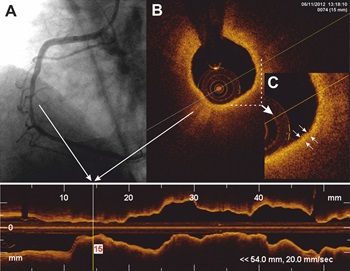

Технологията дава възможност за прецизно изследване на степента и значимостта на запушванията на кръвоносните съдове от атеросклеротични плаки. Иинформацията е много важна в случаите на гранични запушвания за вземане на решение за медикаментозно, интервенционално или хирургично лечение.